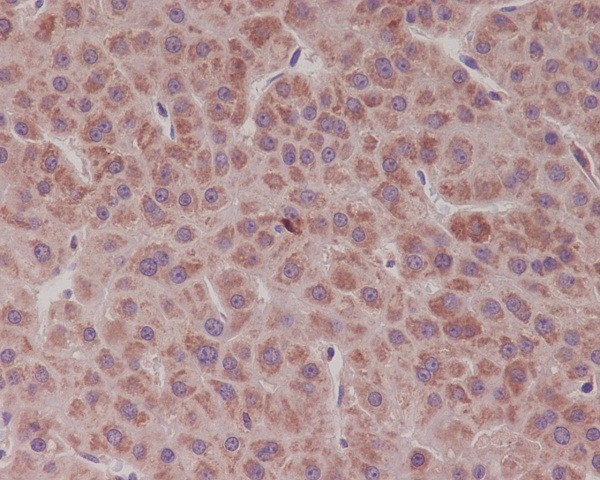

Immunohistochemical analysis of paraffin-embedded human liver cancer, using Bcl-XL Antibody.

Immunohistochemical analysis of paraffin-embedded human liver cancer, using Bcl-XL Antibody.